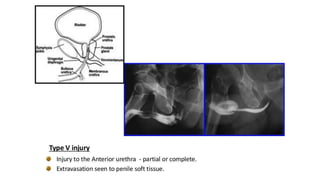

Blunt Urethral Trauma

Classified Anatomically as

โ€ข Anterior

โ€ข Posterior

Anterior urethral injury

โ€ข MC iatrogenic (due to instrumentation)

โ€ข May occur if patient falls on a blunt object or direct injury to perineum

โ€ข Straddle Injury - compression of urethra against anterior pelvic ring

Posterior urethral injury results from

โ€ข A crushing force to the pelvis

โ€ข Is associated with pelvic fractures.